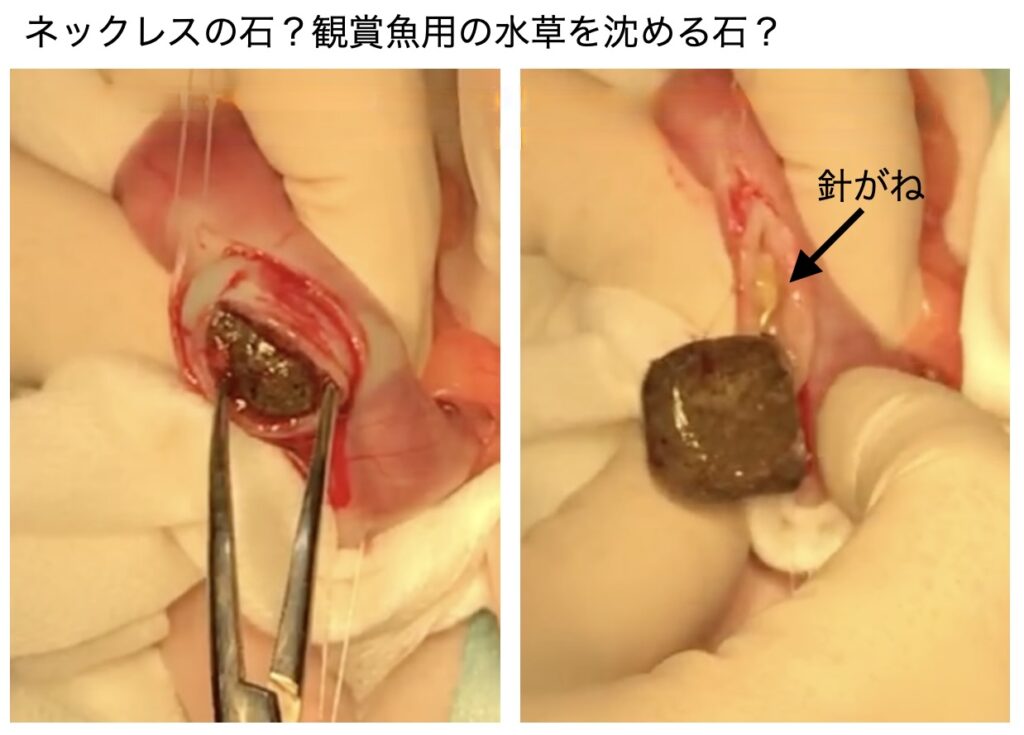

この石のせい?よく見ると石と針金状の異物が確認され、その針金が消化管に刺さって痛みを起こしている可能性はあります。ひょっとしたら足腰が痛い可能性もありますが、消化管内異物によって痛みが生じて歩行異常とヨダレが出てるのでは?と判断し、オーナー様に相談の上異物摘出手術を実施しました。

胃内に1辺が2cmほどの石(観賞魚の水槽で水草をくくりつける石?)人工的な石で針金が飛び出ていました。胃内に異物もあったのでそれも取り出しました(最近流行りの立体シール『ドロップシール』が出てきました)。テレビで見てドロップシールの存在は知っていたのですが手術で摘出した際にはプラスチック片だと思いました。ドロップシールは小学校低学年くらいの児童で人気の立体シール(ぷっくりシール)で、透明樹脂で飴玉のように盛り上がった、つやつやした質感が特徴のデコレーションアイテム。文房具店等では売り切れ続出の人気とのこと・・消化管から出てきた立体シールの絵柄などは確認できませんでしたが、当院スタッフによるとドロップシールだろうとのこと。

1辺が約2cmの石はGoogleの画像検索をしたところ「コンドライト(石質隕石)の可能性が高く、ペンダントやアクセサリーに加工したもの」とのこと!!軽はずみな発言になりますが『なかなかやるねぇ』と術後に感心してしましました。隕石とドロップシール!!何だか洒落たもんを口にするんですね!!凄くないですか??